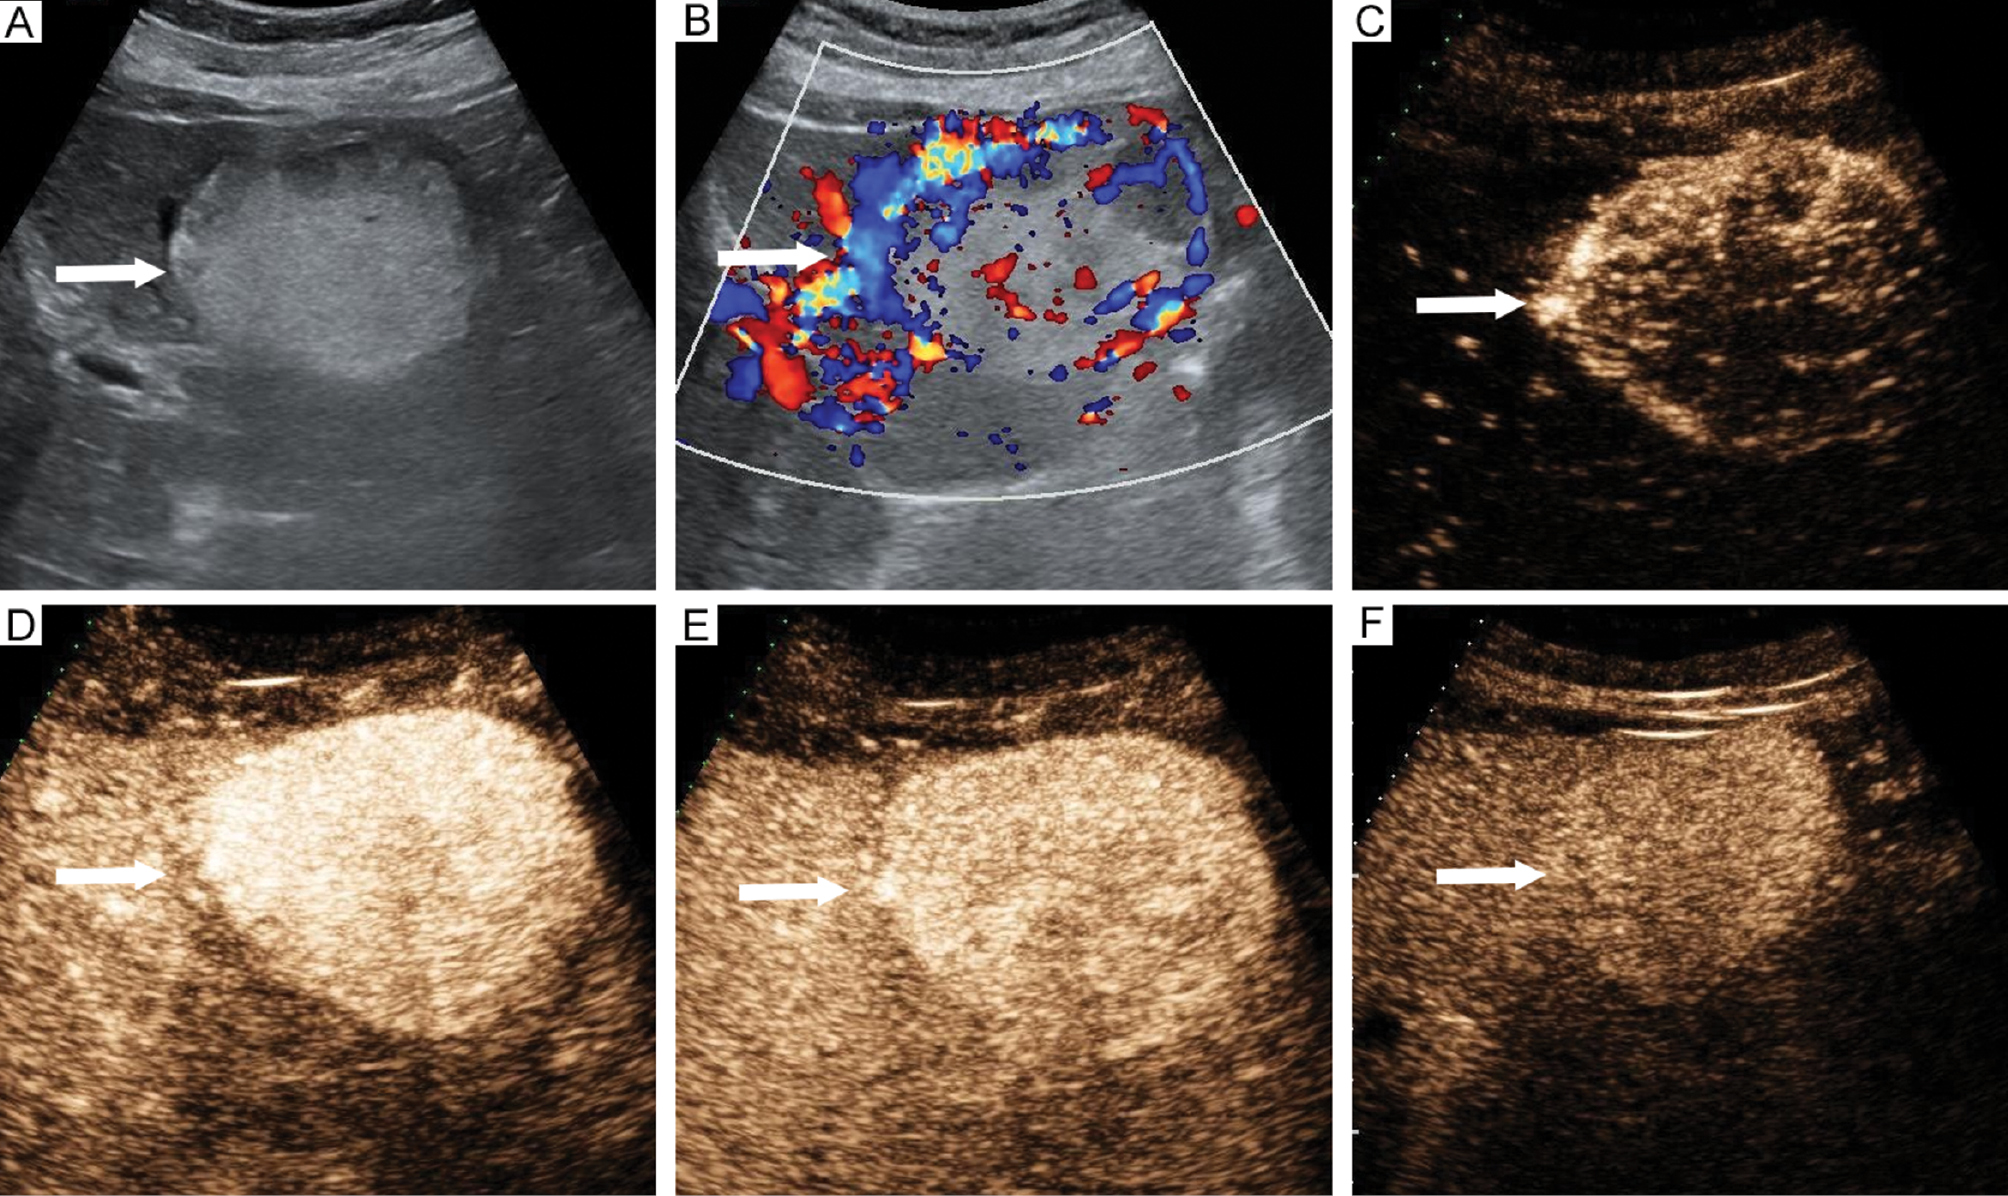

Figure 2 Imaging features of perivascular epithelioid cell tumor in a 69-year-old female. (A) Hyperechoic lesion located in segment 3 (arrow). (B) Presence of larger blood vessels around lesions (arrow). Contrast-enhanced ultrasound revealed (C) Rapid centripetal enhancement at 13 s (arrow), (D) Hyperenhancement in the arterial phase without necrosis at 20 s (arrow), (E) Hyperenhancement in the portal phase at 59 s (arrow), (F) Isoenhancement in the delayed phase at 183 s (arrow).

Figure 3 Imaging features of hepatocellular carcinoma in a 75-year-old male. (A) Hyperechoic lesion located in segment 3 (arrow). (B) Absence of larger blood vessels around lesions (arrow). Contrast-enhanced ultrasound revealed (C) Rapid centripetal enhancement at 15 s (arrow), (D) Hyperenhancement in the arterial phase with necrosis at 24 s (arrow), (E) Hypoenhancement in the portal phase at 67 s (arrow), (F) Hypoenhancement in the delayed phase at 171 s (arrow).

The CUS imaging features of both groups are summarized in Table 2. Significant differences were detected in echogenicity, margins, and the presence of larger blood vessels around lesions between the PEComa and HCC groups (P < 0.05). PEComa lesions were more likely to have a hyperechoic appearance with clear margins and larger blood vessels around lesions compared to HCC lesions (Figures 2 and 3). No significant differences were detected between the two groups with respect to tumor number, location, maximum diameter, morphology, hyperechoic ring, or blood flow on color Doppler imaging (P > 0.05).